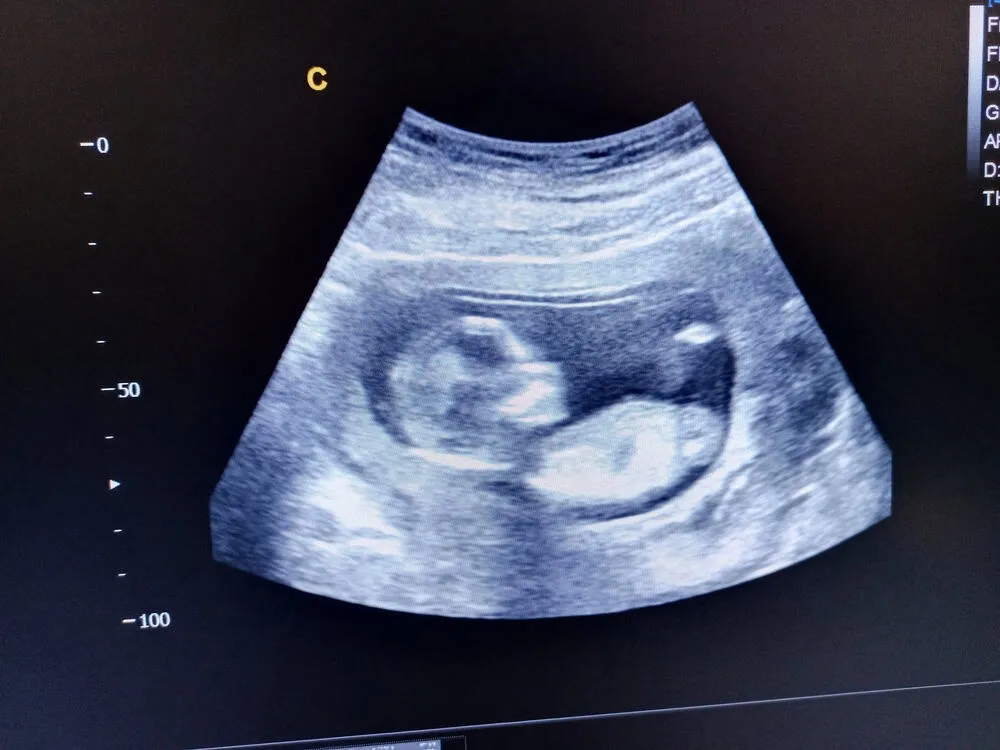

Thai nhi 15 tuần tuổi sẽ bắt đầu mọc lông mày và lông mi. Làn da của bé cũng đang liên tục phát triển, mỏng và mờ đến mức có thể nhìn thấy các mạch máu phía trong. Các đặc điểm giới tính bên ngoài tương đối rõ để nhận diện qua siêu âm.

Thai nhi 15 tuần phát triển như thế nào?

Bạn đang thắc mắc thai nhi 15 tuần tuổi phát triển như thế nào? Thai nhi trong bụng mẹ có kích thước của một quả mơ. Các chỉ số kích thước của con cụ thể như sau:

- Cân nặng khoảng 99-132g.

- Chiều dài từ đầu đến mông khoảng 10,1cm.

Ngoài ra, dấu hiệu thai nhi 15 khỏe mạnh còn gồm các chỉ số sau:

- Đường kính lưỡng đỉnh (BPD): 29mm

- Chiều dài xương đùi (FL): 17mm.

- Siêu âm theo dõi sự phát triển của thai nhi 15 tuần